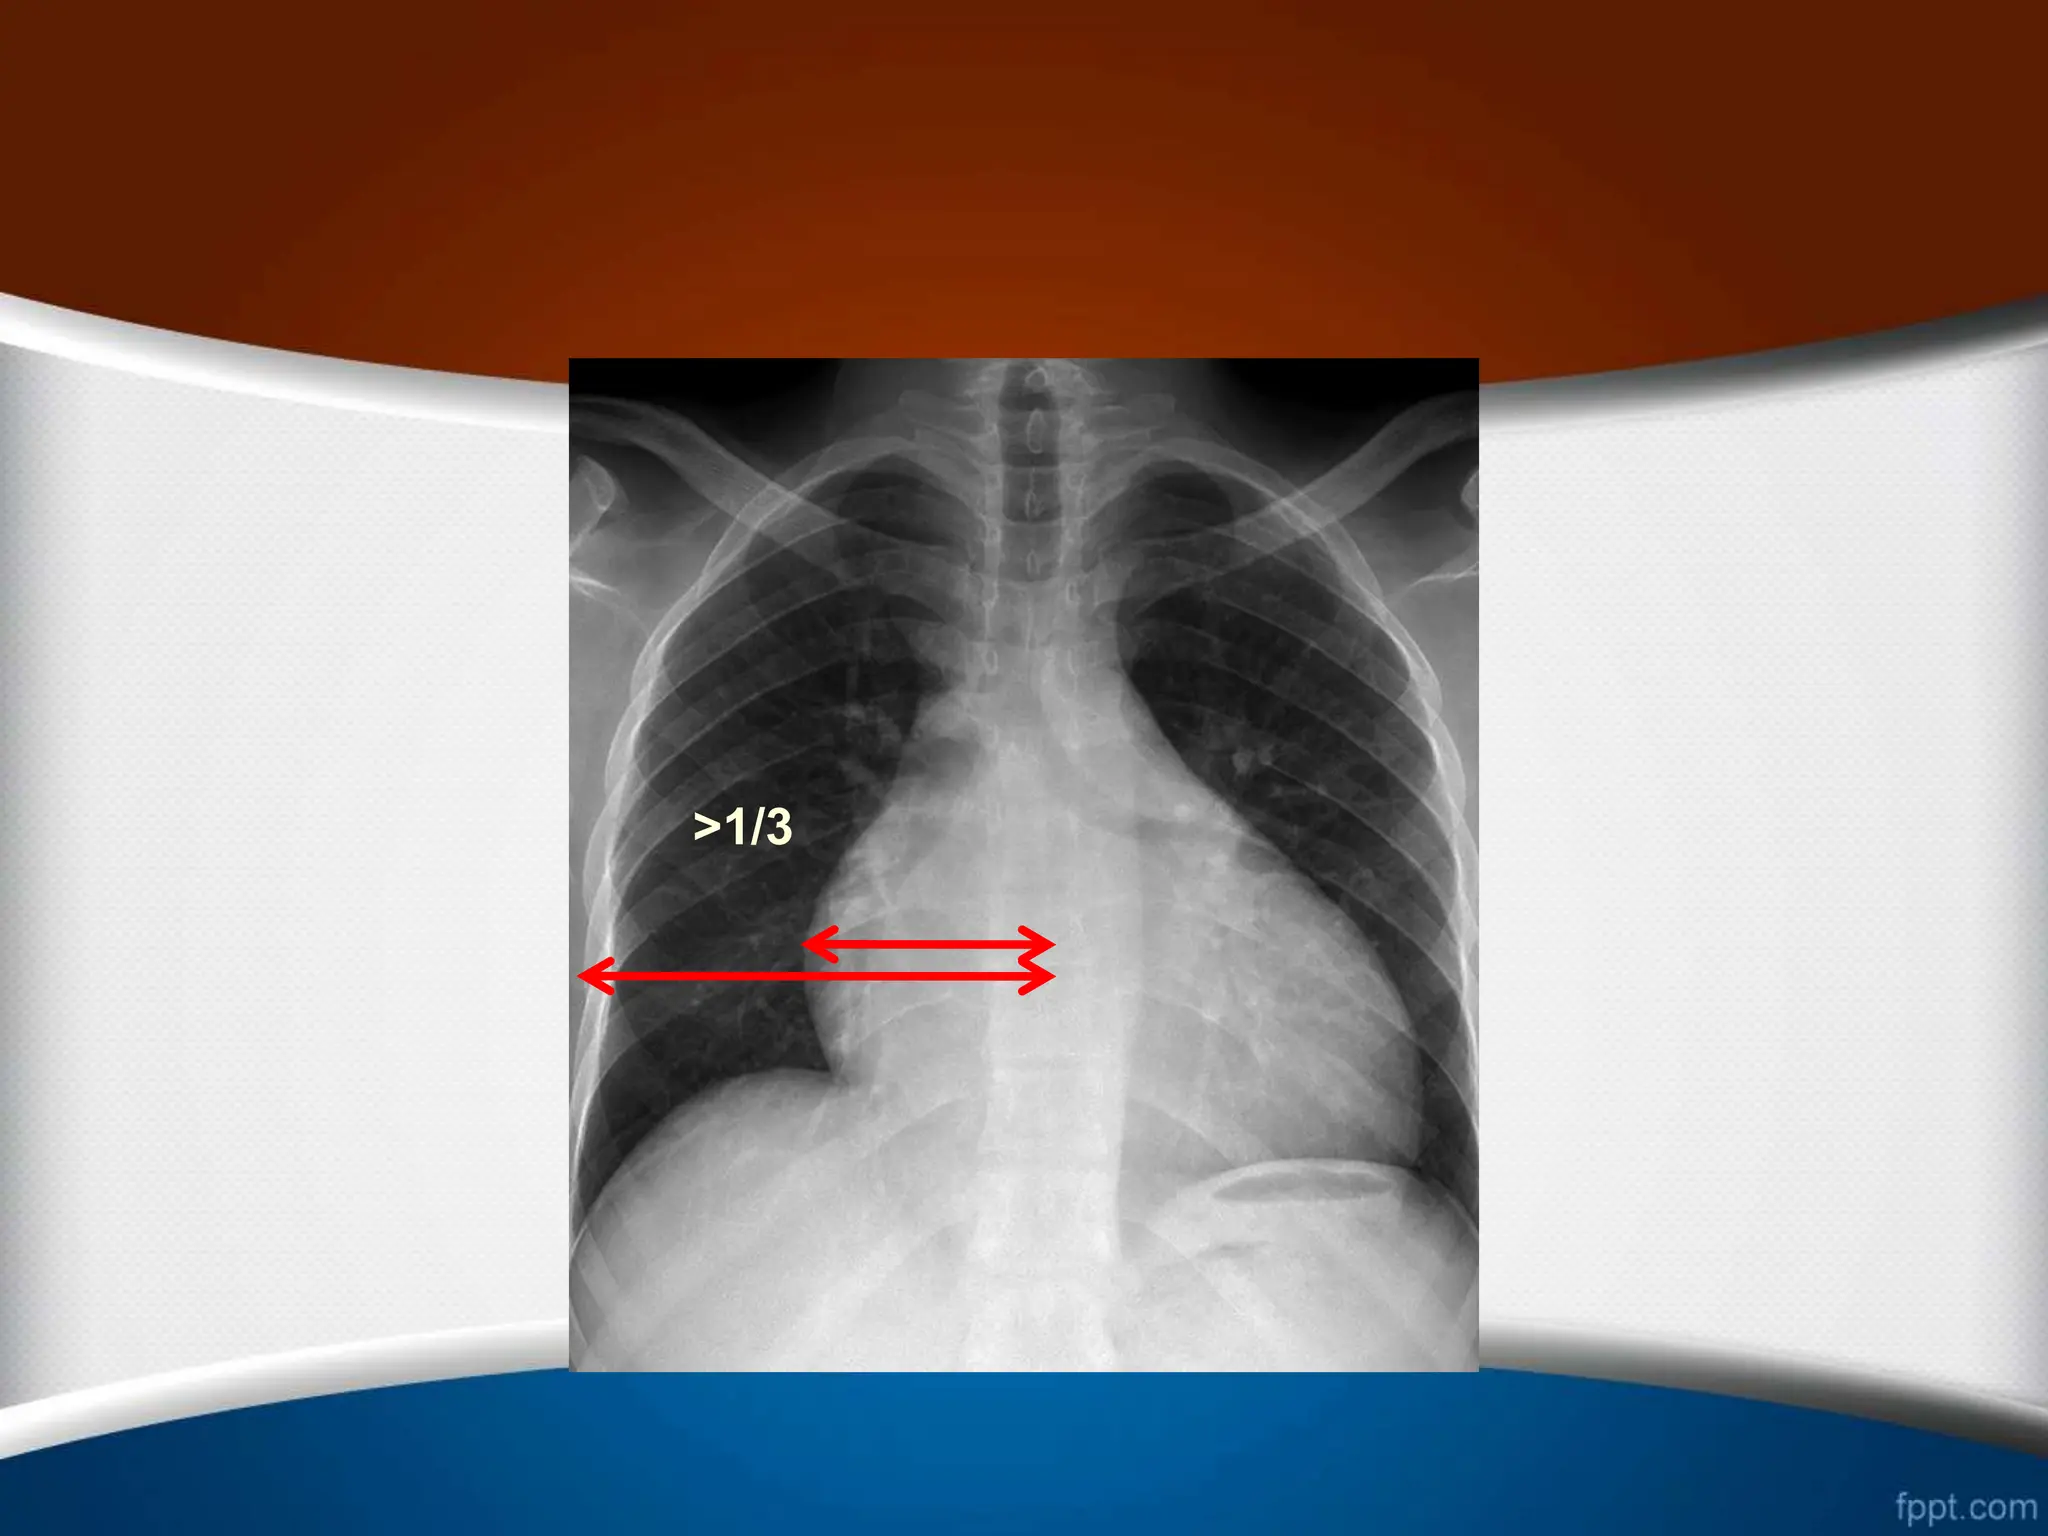

.1

‫از‬ ‫بیشتر‬ ‫قلب‬ ‫راست‬ ‫ی‬ ‫کناره‬ ‫افزایش‬

25

%

‫قلب‬ ‫عرضی‬ ‫دیامتر‬

.2

‫راست‬ ‫کاردیوفرنیک‬ ‫ی‬ ‫زاویه‬ ‫شدن‬ ‫باز‬

(

‫منفرجه‬ ‫یا‬ ‫قائمه‬

)

.3

‫از‬ ‫بیشتر‬ ‫وسط‬ ‫خط‬ ‫از‬ ‫راست‬ ‫دهلیز‬ ‫ی‬ ‫حاشیه‬ ‫بین‬ ‫ی‬ ‫فاصله‬

5.5

‫از‬ ‫بیشتر‬ ‫ها‬ ‫مهره‬ ‫ستون‬ ‫راست‬ ‫حاشیه‬ ‫از‬ ‫و‬ ‫متر‬ ‫سانتی‬

2.5

‫متر‬ ‫سانتی‬

.

.4

‫می‬ ‫تشکیل‬ ‫را‬ ‫توراکس‬ ‫همی‬ ‫سوم‬ ‫یک‬ ‫از‬ ‫بیشتر‬ ‫راست‬ ‫دهلیز‬

‫دهد‬

.5

‫راست‬ ‫دهلیز‬ ‫و‬ ‫صعودی‬ ‫آئورت‬ ‫و‬ ‫راست‬ ‫دهلیز‬ ‫بین‬ ‫ی‬ ‫زاویه‬

‫شود‬ ‫می‬ ‫واضح‬

>5.5cm

>2.5cm

>25%

>1/3